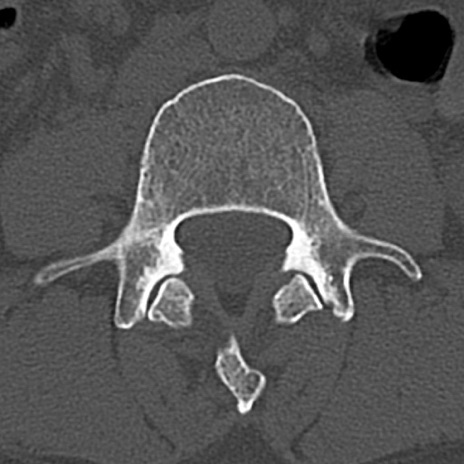

腰椎CT

横断像と矢状断像